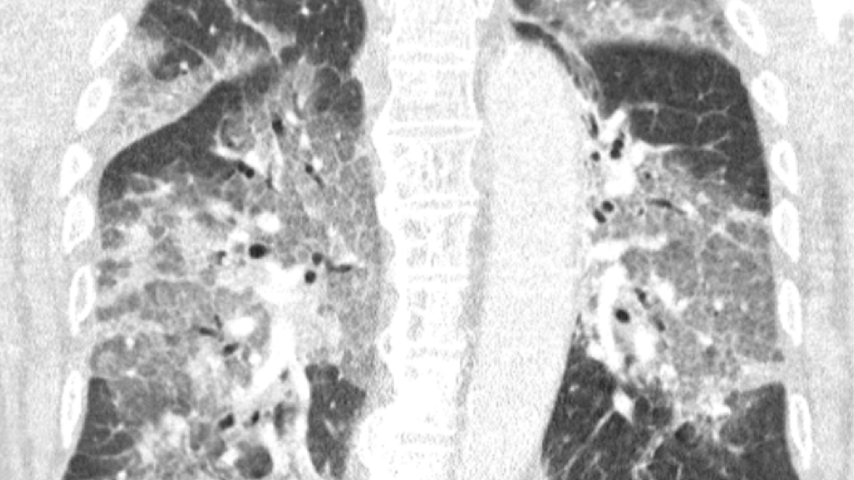

Op de longscan die het ziekenhuis met instemming van de patiënt heeft gedeeld, is de schade aan de longen te zien. "Je hoeft geen longarts te zijn om de verwoestingen te herkennen", staat in de brief.

De CT-scan van een patiënt die had geweigerd het AstraZeneca-vaccin te nemen. | Beeld: Zuyderland ZiekenhuisKamer wil keuzevrijheid